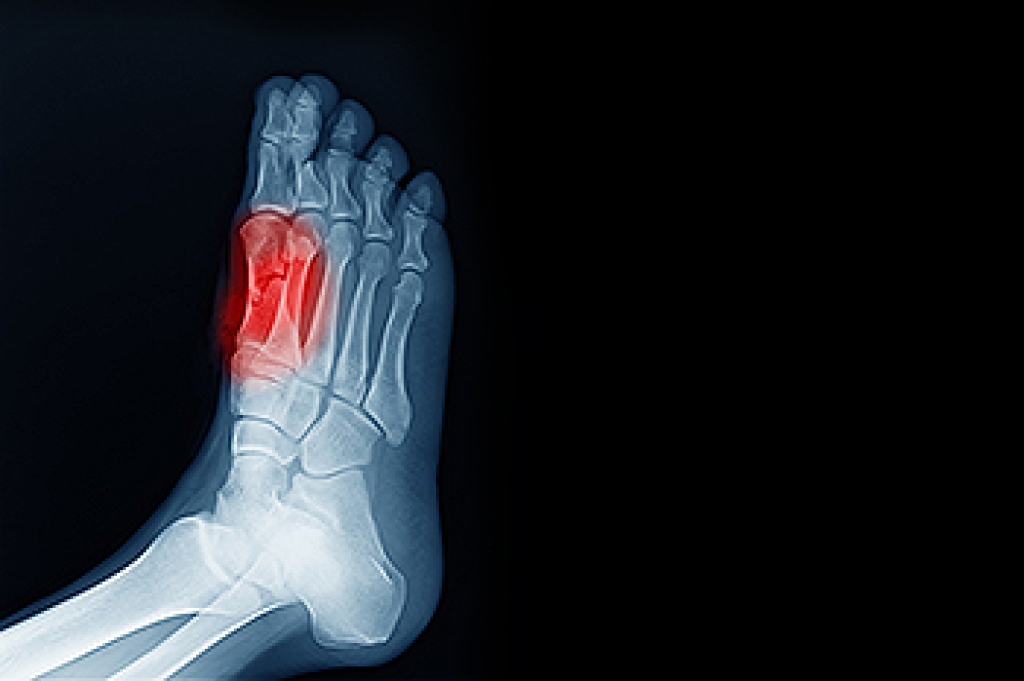

Freiberg’s disease - This can be seen as a deterioration and flattening of a metatarsal bone that exists in the ball of the foot. It typically affects pre-teen and teenage girls, but can affect anyone at any age. Symptoms that can accompany this can be swelling, stiffness, and the patient may limp.